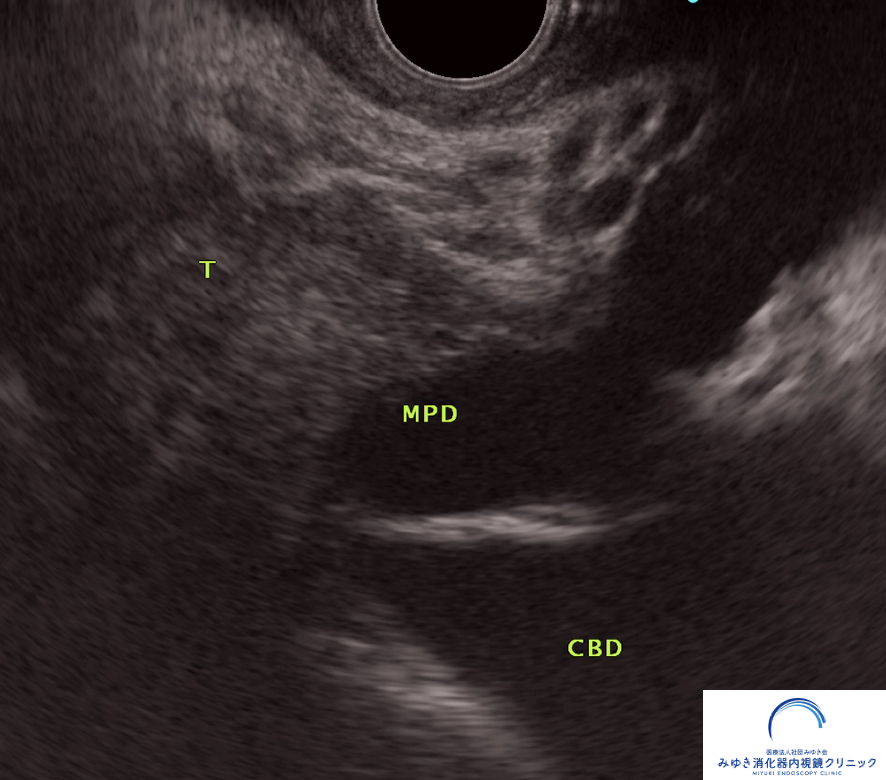

他院の腹部エコーおよびCTで膵管拡張を指摘され、当院で超音波内視鏡(EUS)による精密検査を行いました。

他院の腹部エコーおよびCTで膵管拡張を指摘され、当院で超音波内視鏡(EUS)による精密検査を行いました。 膵臓に約8mmの腫瘍を認め、手術の結果、ステージ1の膵がんと診断されました。 通常の検査では見つかりにくい小さな病変が、EUSによって早期発見につながった症例です。

このように、通常の検査では見つかりにくい小さな膵がんも、EUSによって発見できることがあります。